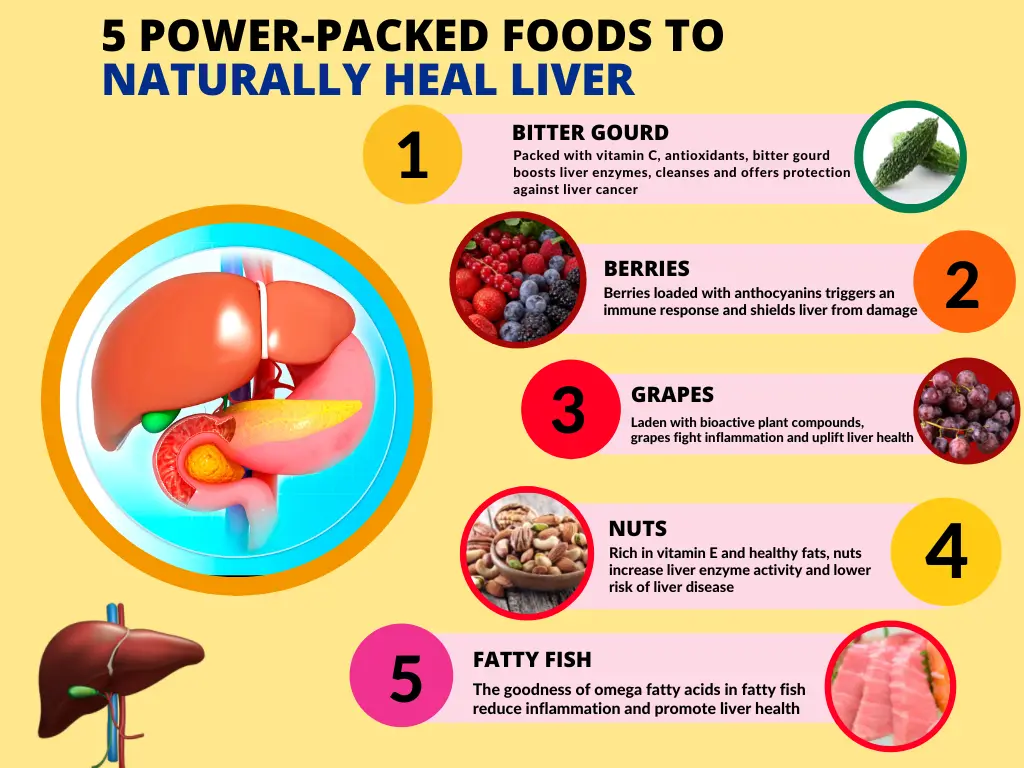

Liver Health 5 Superb Foods That Helps To Boost Liver Function

Liver Health 5 Superb Foods That Helps To Boost Liver Function